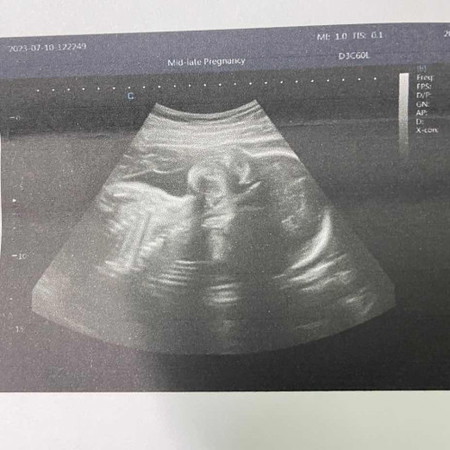

อัลตราซาวด์4มิติ

หมอบอกว่ารกน้องมีตำแหน่งอยู่ตรงหน้าน้องพอดี อัลตราซาวด์4มิติแล้วมองไม่เห็นเลยค่ะ 28+2🥲 อยากเห็นหน้ามากๆ ทำยังไงได้บ้างคะ